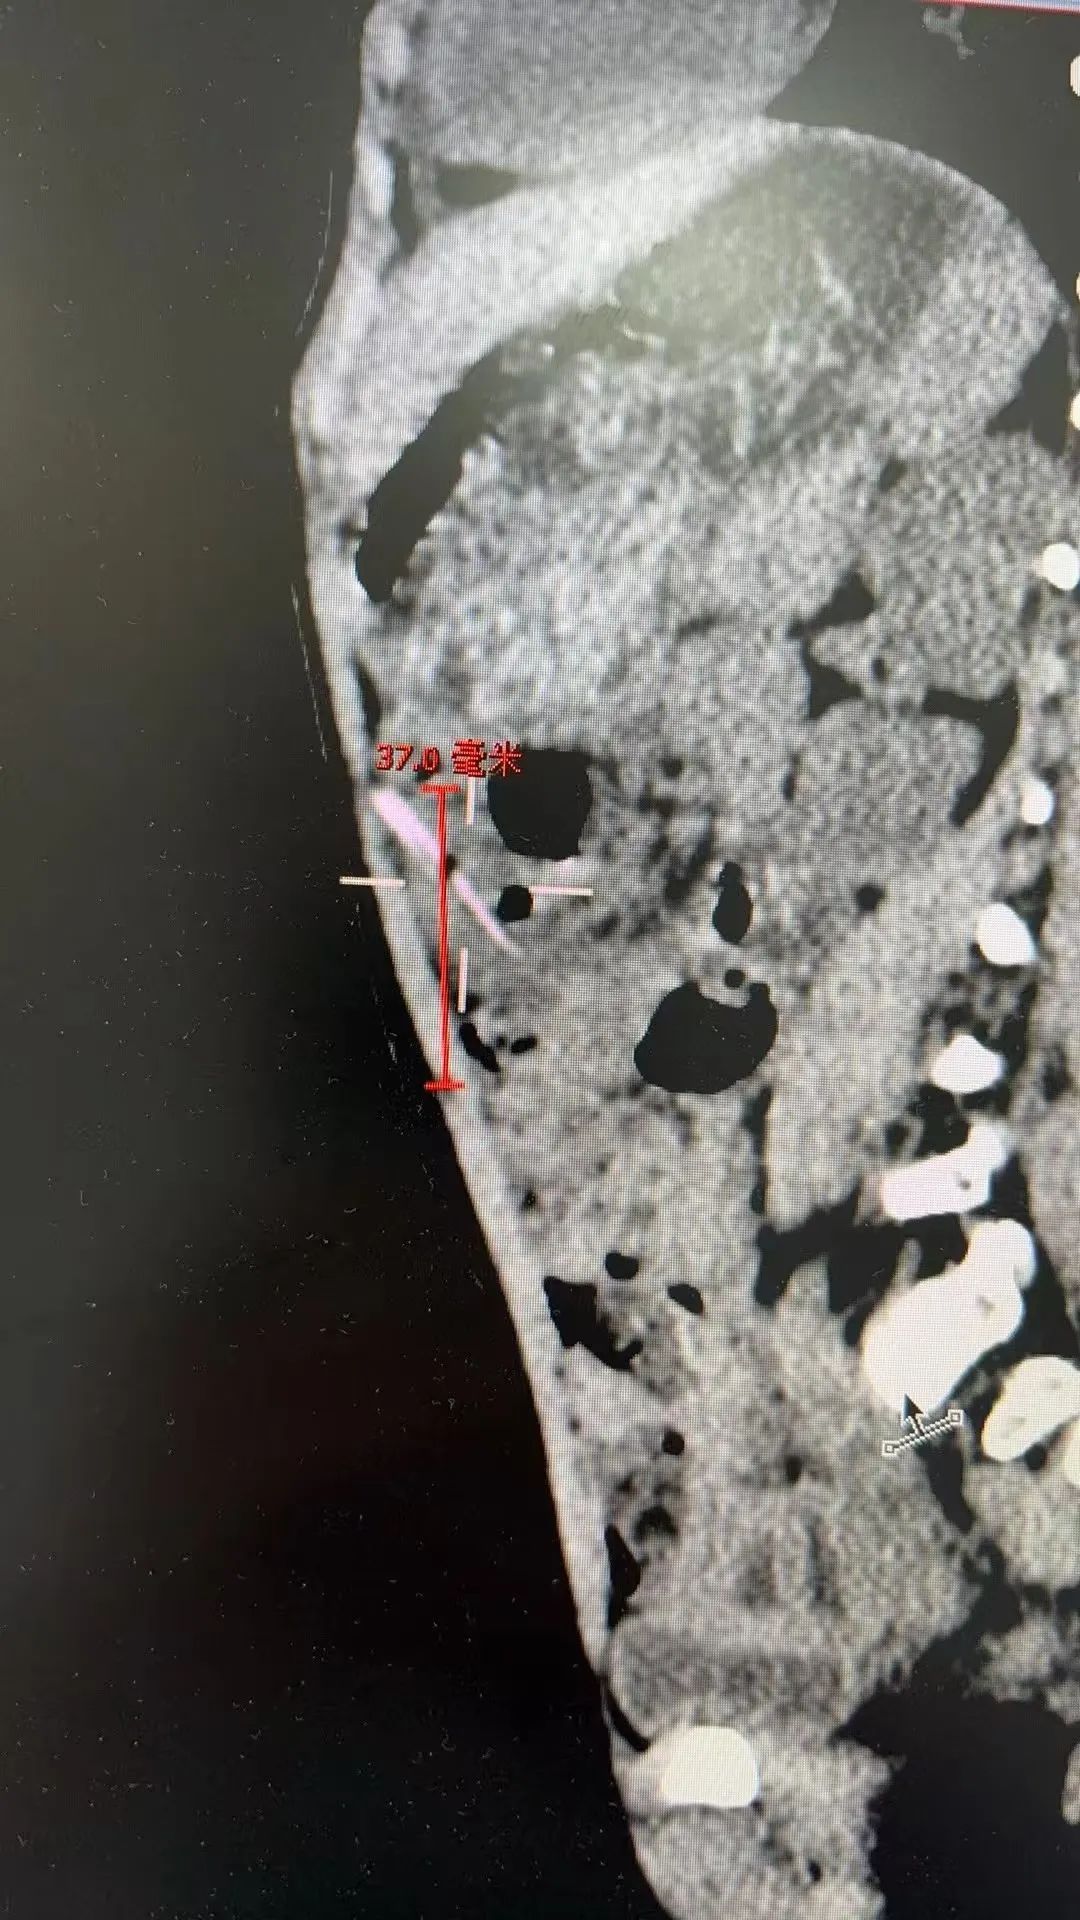

儿童普通外科副主任张伊凡听添添父母讲述了病史,查看孩子并无感冒症状,推测腹痛很有可能与误食异物有关,随后的腹部CT检查发现孩子腹腔内疑似存在约2.5厘米长的异物,张伊凡立即建议孩子住院治疗。

为了避免延误治疗,在征得家长同意后,为添添实施腹腔镜微创手术。术中探查结果令人心惊:一根长约2~3厘米的尖锐竹签,已穿透患儿肠管,深深刺入腹腔!万幸的是,竹签未伤及其他重要脏器,也未引发严重感染。